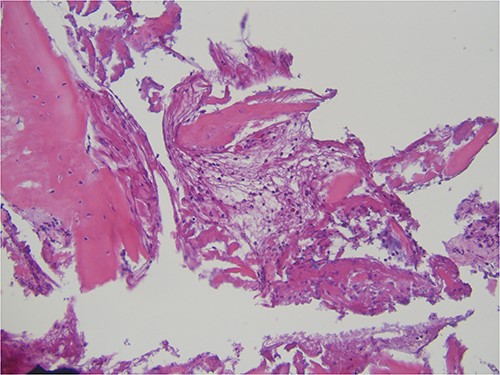

The histopathological analysis reported compact and cancellous bone with signs of remodeling, fibrous medulla, and a slight chronic inflammation compatible with osteomyelitis (Fig. 4). Laboratory results showed elevated liver function test results (due to the long-term antimicrobial therapy) and high inflammatory markers (c-reactive protein) but no change in the blood cell count, especially leucocytes.

Histopathological specimen showing bone with signs of remodeling and chronic inflammation.